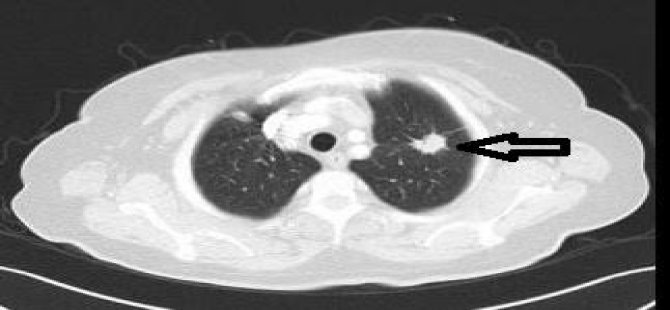

Düşük Doz Bilgisayarlı Tomografi

Prof. Dr. Batırel, akciğer kanseri için tarama testi olarak düşük doz bilgisayarlı tomografinin kimlere yapılması gerektiğine ilişkin, “Uzun yıllar akciğer kanseri için ideal bir tarama testi araştırıldı. Balgam testi, akciğer filmi ile yapılan taramalar istediğimiz neticeleri vermedi. Ama 2000’li yıllarda yapılan ve yaklaşık 25 bin kişinin düşük doz bilgisayarlı tomografi ile taranması neticesinde tespit edilen akciğer kanserlerinin %80’den fazlasının ilk aşamada olduğu ve akciğer kanserine bağlı ölümlerde %20 azalma olduğu ortaya kondu. Halihazırda elimizdeki en önemli tarama testi yıllık düşük dozlu bilgisayarlı tomografi taramasıdır. Bu taramanın 55 yaş üzerindeki ve en az 20 yıl bir paket sigara içmiş veya halen içen kişilere uygulanması önerilmektedir” diye konuştu.